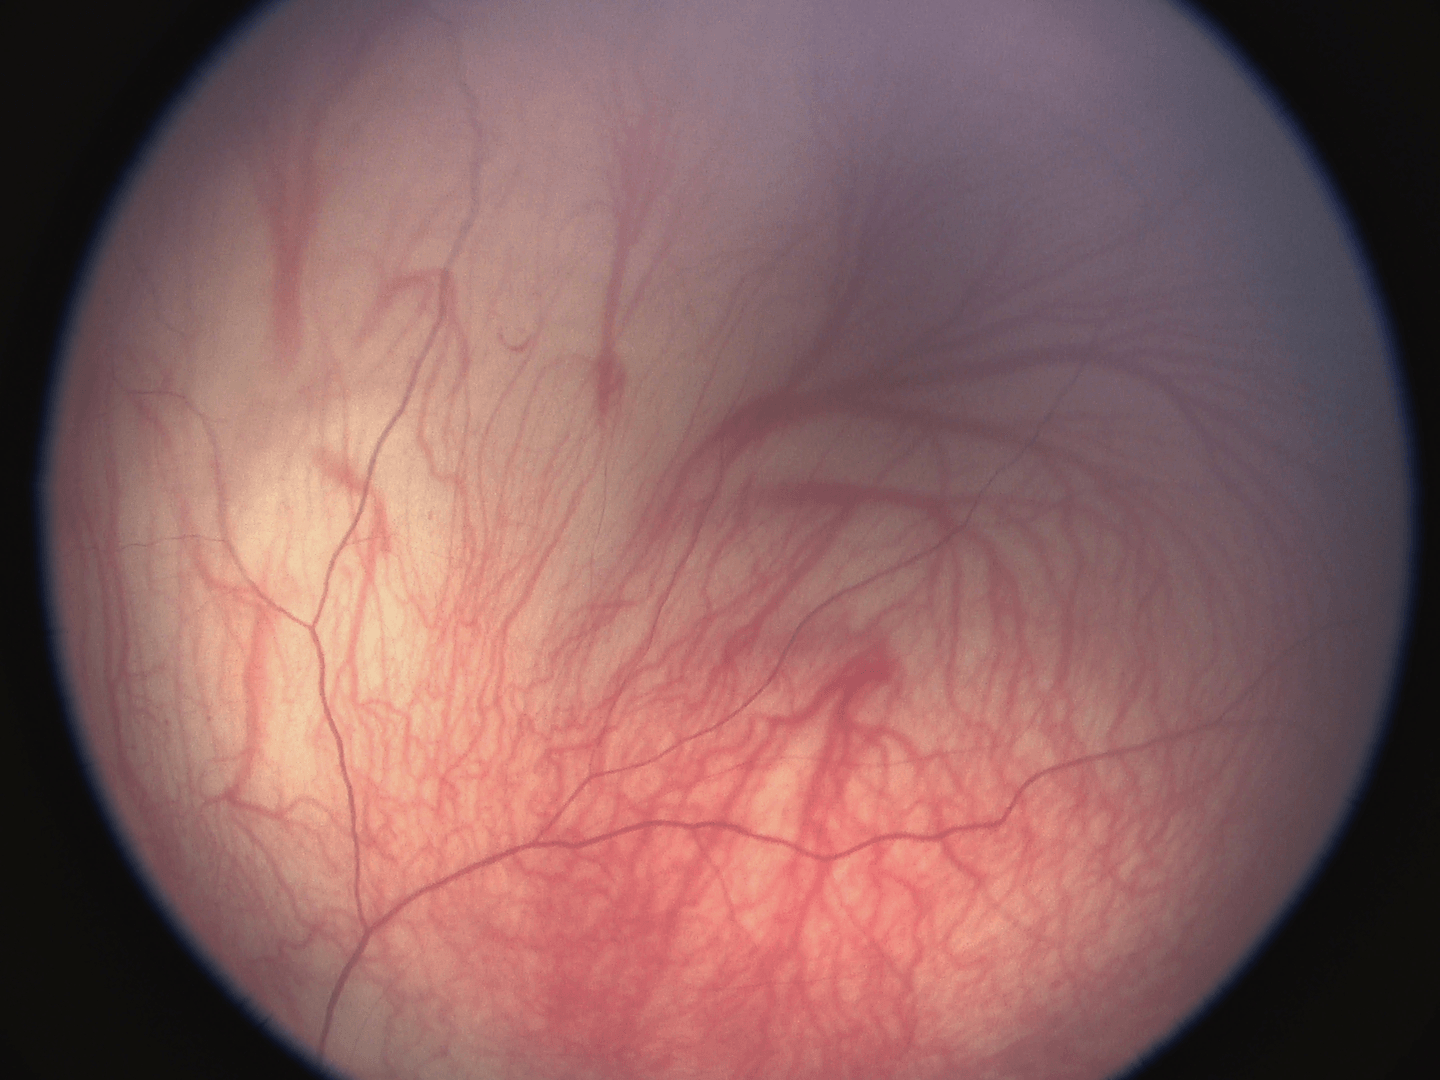

一、高品質(zhì)圖像

采用世界最先進(jìn)的醫(yī)療級3CMOS全高清攝像機(jī)搭配130 o超廣角高品質(zhì)鏡頭,可精密調(diào)焦,確保圖像反映真實飽滿、通透清晰。